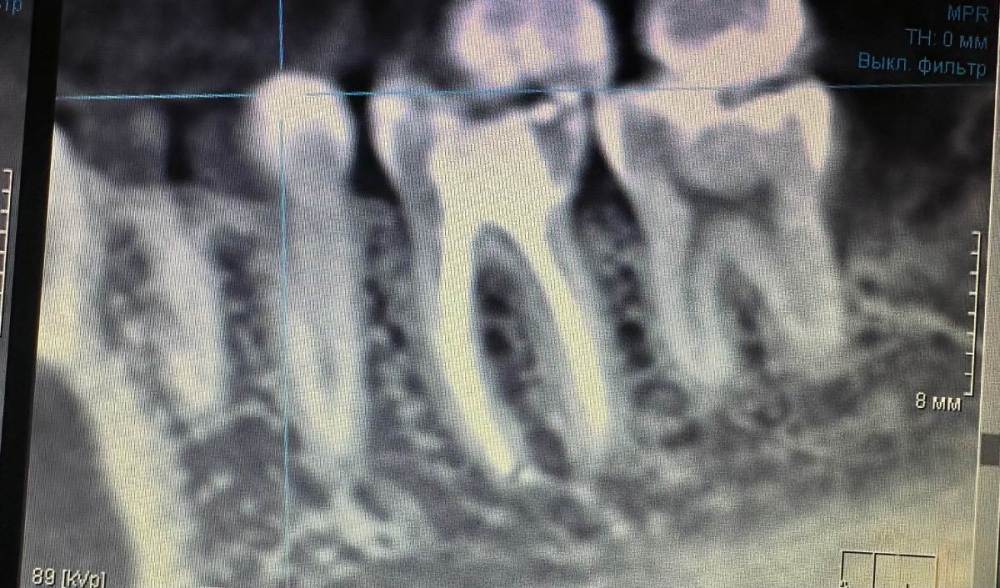

dilya030577 Опубликовано 20 апреля, 2023 Поделиться Опубликовано 20 апреля, 2023 Здравствуйте! Год назад в 6 зубе удалили нервы и уже как год беспокоит этот зуб.Боль ноющая,пульсирующая. В основном начинает болеть после еды и вечером чаще всего.Когда промываю ирригатором,то очень болит десна межу 5 и 6 зубом.Ощущение будто между зубами что-то застряло и хочется поковырять зубочисткой.Что может быть? Ссылка на комментарий

Carioznik Опубликовано 21 апреля, 2023 Поделиться Опубликовано 21 апреля, 2023 12 часов назад, dilya030577 сказал: Боль ноющая,пульсирующая. Возможно, причина в 7 зубе (вроде есть кариес скрытый, если судить по этому скриншоту) Ссылка на комментарий